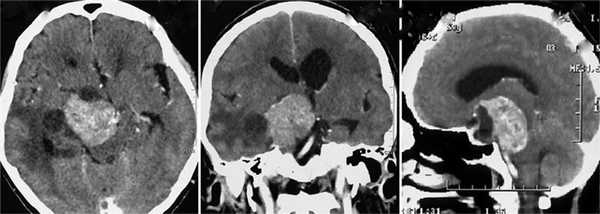

Пациентка Л., 66 лет. Заболевание проявилось генерализованным судорожным приступом в 2012 г. Обследована в НМИЦ нейрохирургии им. Н.Н. Бурденко (от предложенной операции отказалась). Повторно госпитализирована в 2015 г. На СКТ головного мозга (МРТ противопоказана в связи с установленным кардиостимулятором) выявлена большая опухоль в медиальных отделах средней черепной ямки справа и межножковой цистерне, грубо компремирующая ствол головного мозга (рис. 1). Рис. 1. Клинический случай 1. СКТ головного мозга с контрастным усилением в аксиальной, фронтальной и сагиттальной проекциях. Выявляется опухоль медиальных отделов средней черепной ямки справа, межножковой цистерны. Опухоль значительно увеличилась в размерах (старые снимки не сохранились). В неврологическом статусе имелись мнестические расстройства (фиксационная амнезия, снижение критики), гипестезия в зоне иннервации тройничного нерва справа, спонтанный горизонтальный нистагм, мозжечковые нарушения. Глазодвигательных нарушений не было. Учитывая клиническую картину заболевания и данные СКТ головного мозга, была предположена невринома тройничного нерва.